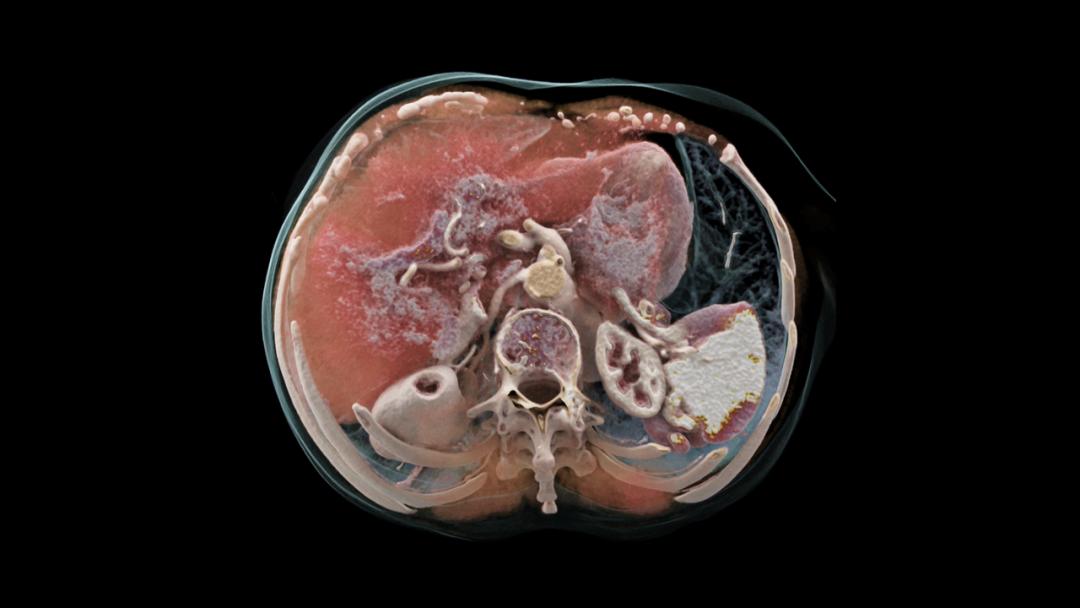

而随着CT技术发展历经近50年,正在从传统的扫描速度和排数(探测器宽度)向能量CT转变。目前能量CT主要包括:双层探测器光谱CT、光子计数CT等。

在肿瘤成像方面, 能量CT可非常精准地识别超早期肿瘤病灶 。

光谱CT领域,飞利浦是全球最早入局的玩家之一:

- 2016年,推出全球首台双层探测器光谱CT;2021年,新一代光谱计数CT——皓克Spectral CT全球发布。

- 2022年5月,皓克Spectral CT通过NMPA认证,在中国市场正式上市。

皓克Spectral CT